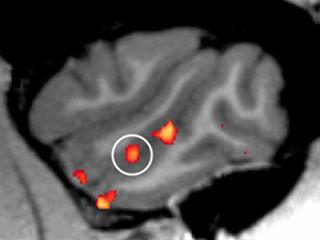

To tease out the distinction between a response to general motion and one specific to faces, Fisher used high resolution scans, known as functional magnetic resonance imaging, to record changes in blood flow in and around the superior temporal sulcus.

He showed the macaques a variety of movies of fellow macaques making expressions - aggressively baring their impressive canine teeth, pleasantly smacking their lips, and making faces as recognizable to macaques as a smile and a grimace would be to a human. All the while, the macaque's head moves, as if turning to address others around it. The researchers made these movies themselves by filming macaques in front of a blue screen. For comparison, Fisher also showed the macaques images of static faces, as well as moving and static objects, such as toys. All five of the previously known facial patches responded preferentially to moving faces over moving objects, suggesting that macaques have neural machinery dedicated to processing both faces and the movement associated with them.

The scans also revealed a surprise: A sixth, previously unknown face patch, which the scientists refer to as the middle dorsal patch. "The middle dorsal patch turned up sporadically in response to static faces, but as soon as we started showing moving faces, it reliably appeared in each brain hemisphere for every macaque," Fisher said. "A similar movement-preferring patch has been identified in humans, and it appears that the middle dorsal patch could be the macaque equivalent."